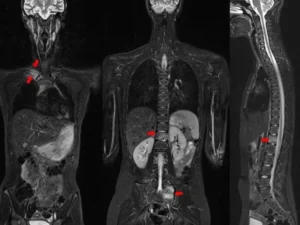

Tüm vücut MR, manyetik rezonans görüntüleme teknolojisi kullanılarak vücudun tamamının ayrıntılı bir şekilde taranmasıdır. Radyasyon içermeyen bu yöntem, manyetik alan ve radyo dalgaları yardımıyla organların ve dokuların yapısını detaylı bir şekilde gösterir. Doktorlar, bu görüntüleri kullanarak hastalıkları teşhis eder ve tedavi planlarını oluşturur.

Tüm vücut MR, genellikle hastalıkların erken teşhisi ve yayılımının değerlendirilmesi amacıyla çekilir. Özellikle kanser taramaları, inflamatuar hastalıklar, enfeksiyonlar ve dejeneratif hastalıkların tespitinde kullanılır. Ayrıca, vücutta mevcut olan anormalliklerin detaylı bir şekilde incelenmesi için de tercih edilir.

Tüm vücut MR, kanser şüphesi olan hastalarda, inflamatuar hastalıklarda, enfeksiyonların yayılımını belirlemek için ve dejeneratif hastalıkların teşhisinde kullanılır. Ayrıca, kronik ağrıların kaynağını tespit etmek, sinir sistemi hastalıklarını ve damar problemlerini değerlendirmek amacıyla da uygulanabilir.

Tüm vücut MR ile kanser türleri, tümörlerin yayılımı, inflamatuar hastalıklar, enfeksiyonlar, dejeneratif hastalıklar, sinir sistemi bozuklukları ve damar hastalıkları teşhis edilebilir. Bu yöntem, özellikle erken teşhis gerektiren hastalıklarda büyük önem taşır ve doktorların doğru tedavi yöntemini belirlemelerine yardımcı olur.